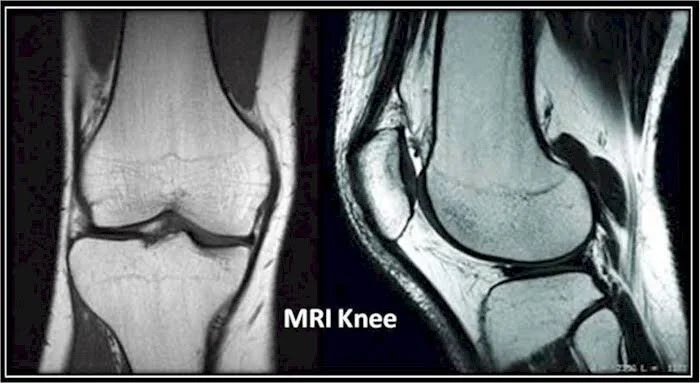

This is a common occurrence. MRI being self-prescribed by active and non-active people with few days of knee pain, or by their treating doctors. They then panic on seeing the reports. Almost always surgery is recommended. What is it that the latest research suggests?

A London based study published in Skeletal Radiology on 14th February 2020, looked at how often would MRIs show abnormal findings in knees of adults who had no complaints. High quality MRI was done for 115 uninjured sedentary adults with average age of 44 years.

Surprisingly both knees of almost all of these individuals showed one or the other abnormality for which under normal circumstances surgery is recommended when presented with pain.